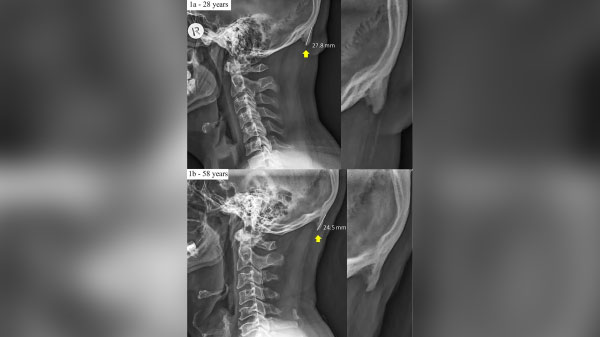

ऑस्ट्रेलियन यूनिवर्सिटी ऑफ द सनशाइन कोस्ट के स्वास्थ्य वैज्ञानिक डेविड शाहर का कहना है, '' मैं 20 वर्षों से एक चिकित्सक हूं और पिछले एक दशक में, मुझे अपने रोगियों की खोपड़ी में बढ़ती हुई हड्डी दिखाई दे रही है। Scientific Report की रिपोर्ट में डेविड के मुताबिक इस हड्डी में स्पाइक जैसी विशेषता पाई जाती है, जिसे मेडिकल टर्म में "एक्सटर्नल ओसीसीपिटल प्रोटबेरेंस" के रूप में भी जाना जाता है। अगर आपके गर्दन में ये होगा तो आप इसे छूकर महसूस कर पाएंगे या नहीं तो आप गंजे पर होने पर इसे ध्यान से देख पाएंगे।

2016 में, शाहर और उनके सहयोगियों ने जर्नल ऑफ़ एनाटॉमी में इस घटना की जांच करते हुए एक अध्ययन किया। उन्होंने 18 से 30 साल के बीच के 200 से अधिक रेडियोग्राफ़ रोगियों का विश्लेषण किया, और उनमें से 41 प्रतिशत में स्पाइक यानि हड्डी को बढ़ा हुआ पाया। उन्होंने रिसर्च में पाया कि महिलाओं की तुलना में पुरुषों में स्पाइक ज्यादा पाए गए। उनमें एक रोगी को सबड़े बड़े स्पाइक थी जिसकी लेंथ 1.4 इंच थी।

डॉ शाहर ने इस शोध को करीब 1200 लोगों पर किया और उनमें से 33% लोगों के गर्दन में स्पाइक्स पाए गए। यह स्पाइक खासतौर पर सबसे ज्यादा 18 से 30 साल की आयु वाले युवा और युवतियों में पाए गए हैं। अब शाहर ने अपनी रिचर्स रिपोर्ट में ऐसा नहीं कहा कि स्पाइक्स पाने वाले लोगों को स्पाइक स्मार्टफोन के ज्यादा इस्तेमाल से ही हुई हैं।